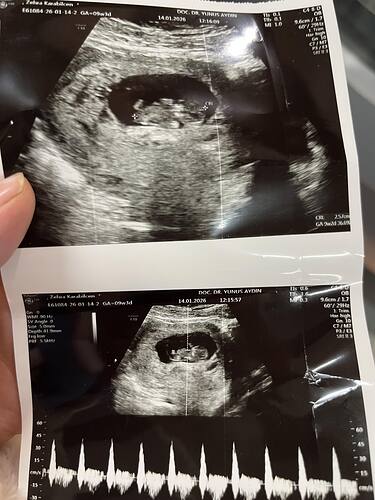

Çok tesekkur ederim simdilik 11 haftalık haftaya kontrolüm var.doktor yeni doğum yaptığımı öğrenince plasentada yapışıklık var mı diye detaylı bakacak.Çok korkuyorum bu defa.Ardımda küçük bebeğimi bırakıp doğuma gideceğimi düşününce çok üzülüyorum.Çok psikolojim bozuk henüz bebek haberini ne çocuklarıma ne aileme soyleyebildim.Sadece esım bilıyor.3.bebeğimizi isteyerek doğurdum onda bile herkes her yorumu yaptı bunda düşünemiyorum![]()